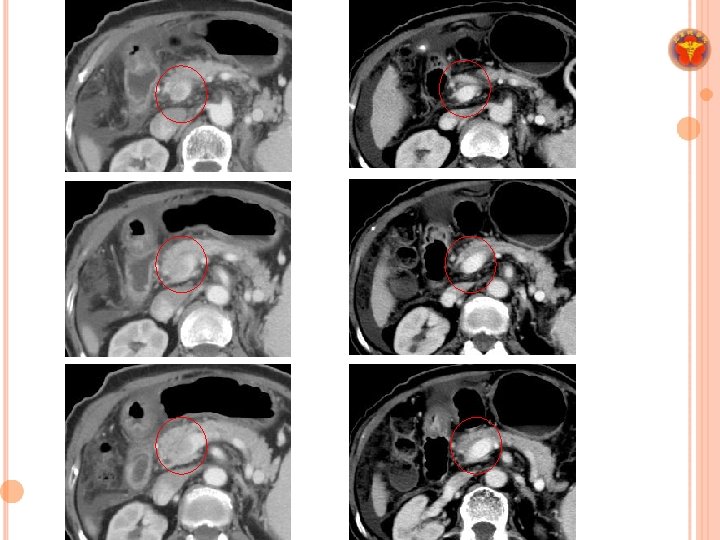

SABR FOR LIVER CANCER INTSGH ¢ Research overview 1. Indications (safety and efficacy) (1) Recurrent HCC (Int J Radiat Oncol Biol Phys 2012) (2) TACE-failed HCC (European Journal of Gastroenterology & Hepatology 2014) (3) Re-irradiation for HCC (Journal of Gastroenterology and Hepatology 2014) 2. Identify prognostic indicators (1) 18 F-FDG PET parameters (J Nucl Med 2013) 3. Image response evaluation (1) Radiographic response evaluation for PVTT (Therapeut Radiol Oncol 2016) (2) Functional image biomarker (DWI) (Ongoing) 4. Other than HCC (1) SABR for Cholangiocarcinoma (2017 Tumori, Epub) 5. Development and validation of nomogram for treatment outcome (1) For BCLC stage C disease (International study under ALRT SIG) SIG 6. Immunological biomarkers before and after SABR (1) Tim-3, PD 1, PD L 1 (ongoing)

MATERIALS &METHODS ¢ A retrospective cohort study ¢ Between December 2007 and July 2015 ¢ BCLC stage C disease ¢ Child-Turcotte-Pugh class A–B

RESULTS ¢ 110 patients with 148 tumors ¢ 1 -year in-field control rate: 76. 9% 3 -year in-field control rate: 66. 4% ¢ 1 -year OS: 49. 6% 3 -year OS: 23. 6%